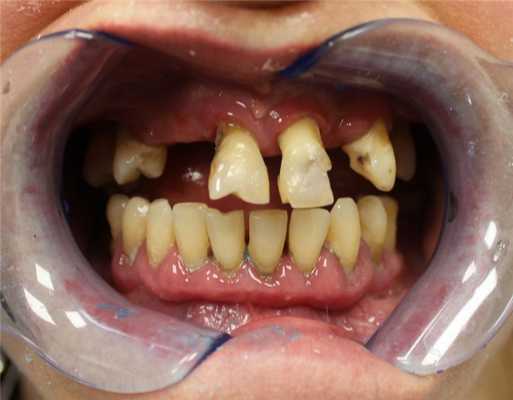

Пациентка обратилась в клинику “Центр несъемного зубного протезирования” с жалобами на отсутствие зубов, нарушение жевания, неудовлетворительную эстетику, подвижность оставшихся зубов. Основными пожеланиями пациентки были: «ни дня без зубов» (наличие адекватной временной конструкции на любом этапе лечения), минимум вмешательств и визитов в клинику, несъемное протезирование обеих челюстей по окончании лечения. После сбора анамнеза и обследования был поставлен диагноз: хронический генерализованный пародонтит тяжелой степени (фото 1 - 3). Пациентке было предложено лечение с использованием дентальных и скуловых имплантатов в 2 этапа.

Хронический генерализованный пародонтит средней степени тяжести в стадии обострения (фото до лечения)